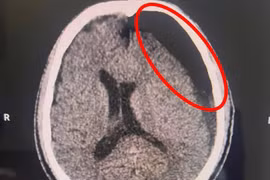

Ngã xe “tưởng nhẹ”, sau 2 tháng mới đau đầu, hôn mê

Kết quả chẩn đoán cho thấy người bệnh bị tụ máu dưới màng cứng bán cấp, tình trạng nguy hiểm có thể dẫn tới tử vong nếu không được can thiệp kịp thời.